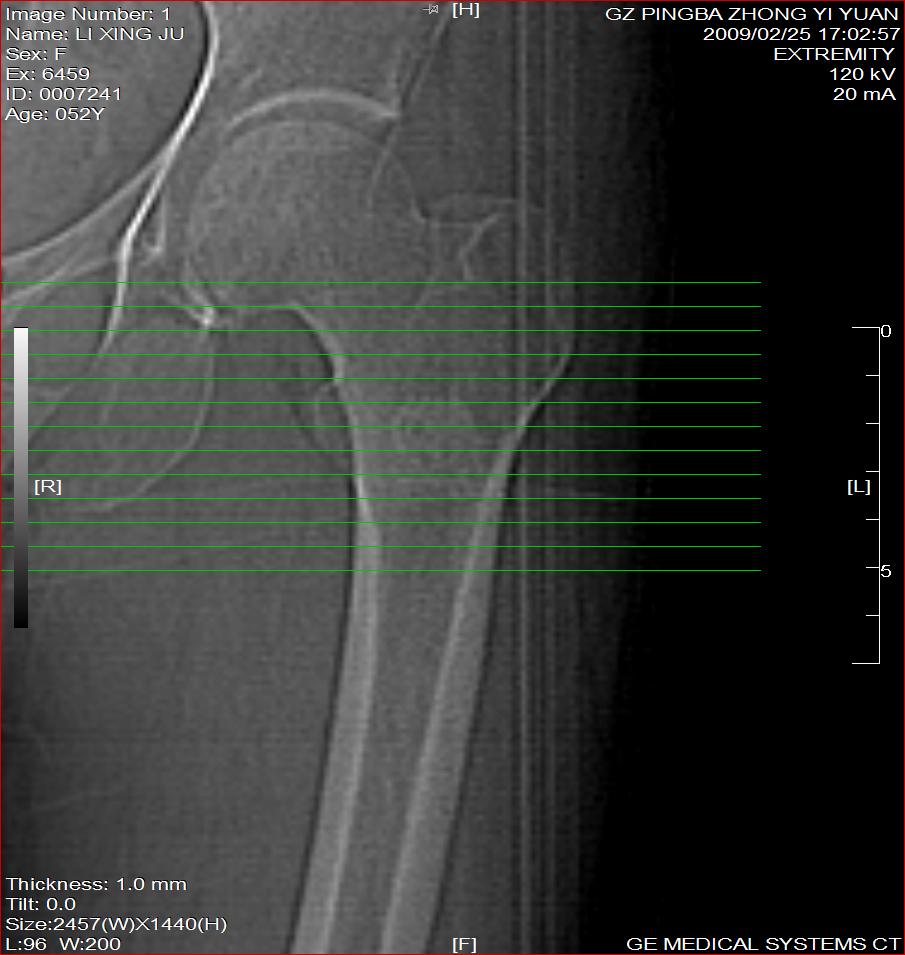

标题: CT18521:左大腿疼痛不适1+月 [打印本页]

标题: CT18521:左大腿疼痛不适1+月

考虑-----股骨骨化性纤维瘤可能性大,不除外---局限性骨纤

考虑:左股骨骨化性纤维瘤

考虑 左股骨骨化性纤维瘤。

考虑:左股骨骨化性纤维瘤。